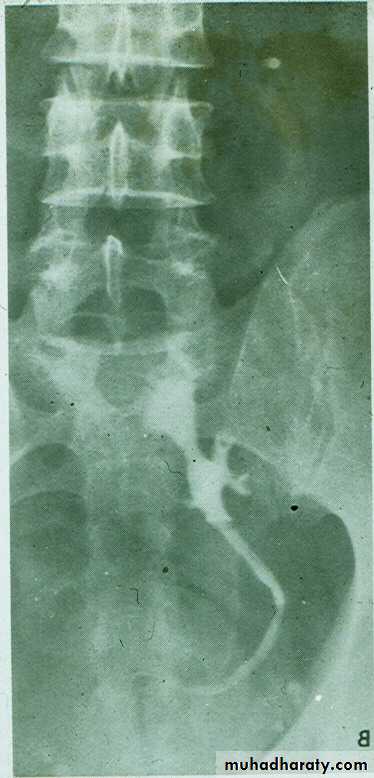

On IVU :

*There is rounded or elliptical dilatation of lower end of ureter with thin lineal filling defect around it , resembling (cobra head appearance) .

*Proximal dilatation of rest of ureter .

* In advanced cases hydronephrosis .

* In obstructed ureterocele filling defect in the bladder

URETEROCELE